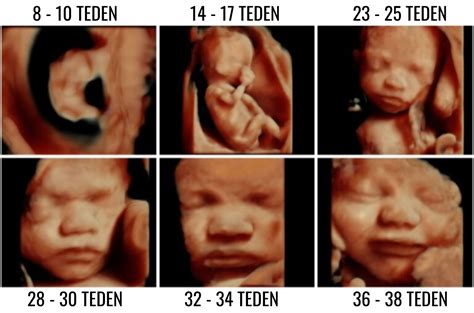

V 21. in 24. tednu nosečnosti ste v drugem trimestru nosečnosti. To je tudi čas za ultrazvočno morfologijo, ki se običajno opravlja med 20. in 22. tednom gestacije. Če se boste odločili za ultrazvok v tem tednu, bo nadvse zanimiv! Ne le, da boste videli otročka na zaslonu, videli boste lahko tudi nekaj čudovitih podrobnosti, kot so možganske poloble in srčni prekati.